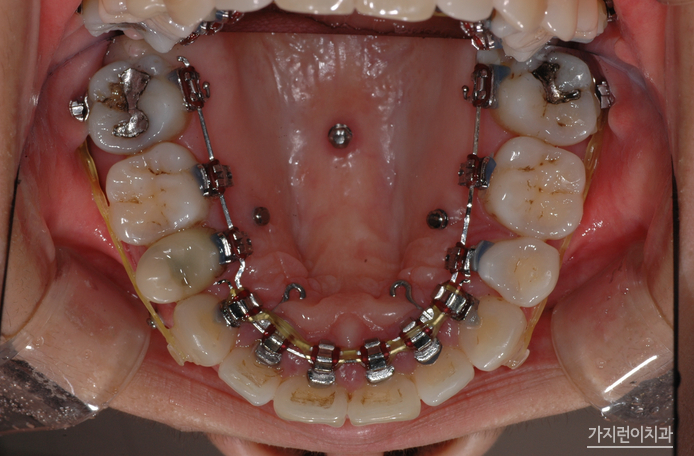

탄댐설측교정으로 교정을 진행한 환자 분

돌출입의 경우 순측으로 진행하게 될 경우 장치로 인해 교정 도중 입이 더 튀어나와보이는 양상이 생겨날 수 있었는데요. 교정 기간 동안 스트레스 받이 교정을 하기 위해 설측으로 진행하려는 분들이 많습니다. 환자분 역시 골격부분을 삭제하는 수술 후에 설측교정방식을 채택해주셨는데요. 일반적인 설측교정과 달리 특허를 받은 장치기 때문에 2개의 와이어를 사용해 안정적인 교정힘을 줄 수 있었습니다. 그렇다면 교정 후의 모습은 어떨까요?